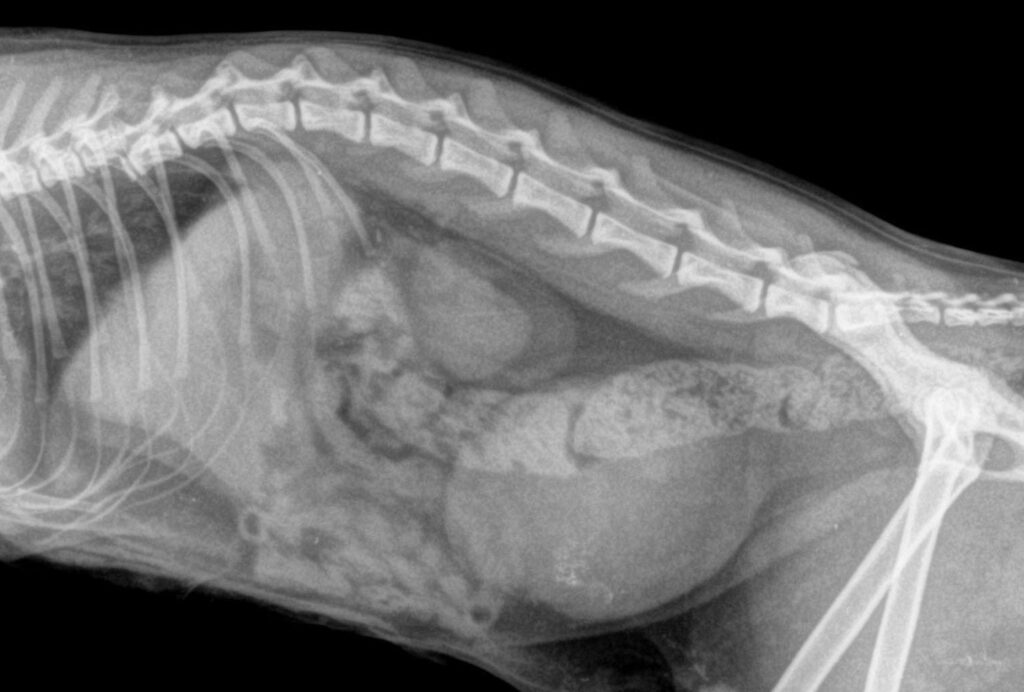

Πλάγια ακτινογραφία της σπονδυλικής στήλης που απεικονίζεται εξάρθρημα μεταξύ των σπονδύλων Θ10-Θ11και κάταγμα της τελικής πλάκας του Θ10. Η διατομή του νωτιαίου μυελο΄ύ είναι πλήρης.